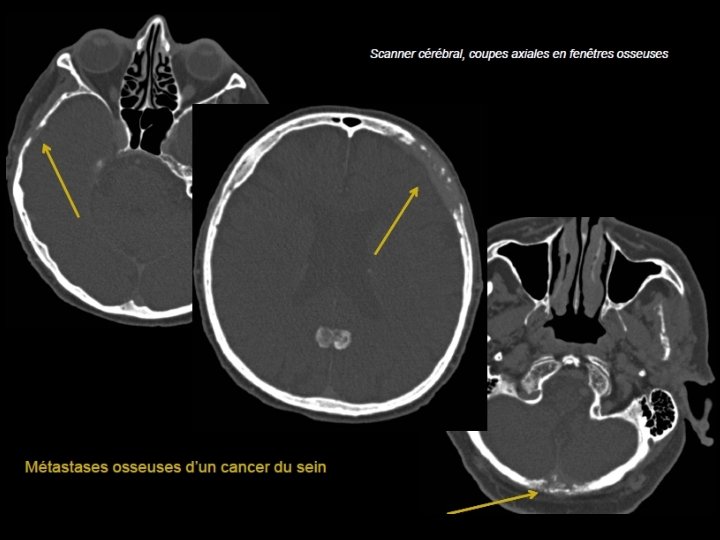

Métastases • Cause la plus fréquente des tumeurs de la voûte • À partir de la 5ème décade • PPRST+++: poumon, prostate, rein, sein, et thyroïde. • Lésions multiples : sein et poumon • Lésion unique, soufflante : rein et thyroïde • Enfant : Neuroblastome étiologies à évoquer en 1 er

• Scanner: - Plus volontiers lacunaires que condensantes. - Initialement diploïques - Destruction secondaire des tables interne et externe - Envahissement des parties molles et de l’espace épidural • IRM - T 1: Hypo ou isosignal effaçant l’hypersignal habituel du diploé, - T 2: Hypersignal - Prise de contraste.